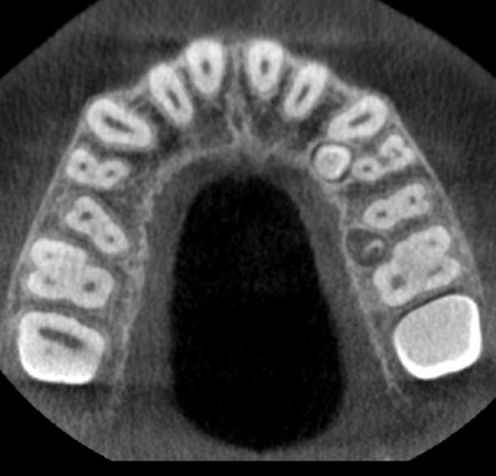

Introducing the CS 9300 Premium Panoramic, Cephalometric, and Cone Beam System from Carestream Dental – your ultimate solution for top-quality dental imaging. This state-of-the-art machine offers both 2D panoramic and cephalometric dental X-rays, as well as adjustable 3D cone beam images in up to seven different field of view sizes, extending up to 17x13.5 cm. This comprehensive range of imaging capabilities makes it a versatile tool, perfect for supporting a wide array of dental, surgical, or orthodontic examinations.

The CS 9300 is a multimodality imaging system that offers a wide range of 2D and 3D imaging options.

The CS 9300's 2D panoramic x-ray imaging capabilities are powered by variable focal trough technology, which provides optimal clarity for every image. The system's 3D imaging capabilities are based on cone beam technology, which delivers high-resolution images with a low radiation dose.

The CS 9300 is a versatile imaging system that can be used for a wide range of dental applications, including: